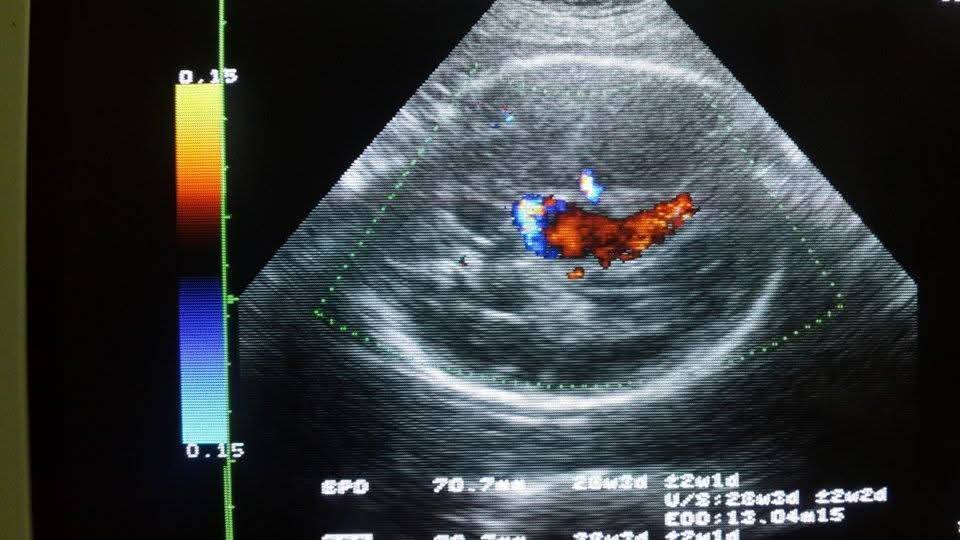

doppler imagies

Doppler ultrasound provides critical information about the blood flow within vessels and tissues, enabling precise diagnosis of vascular conditions.